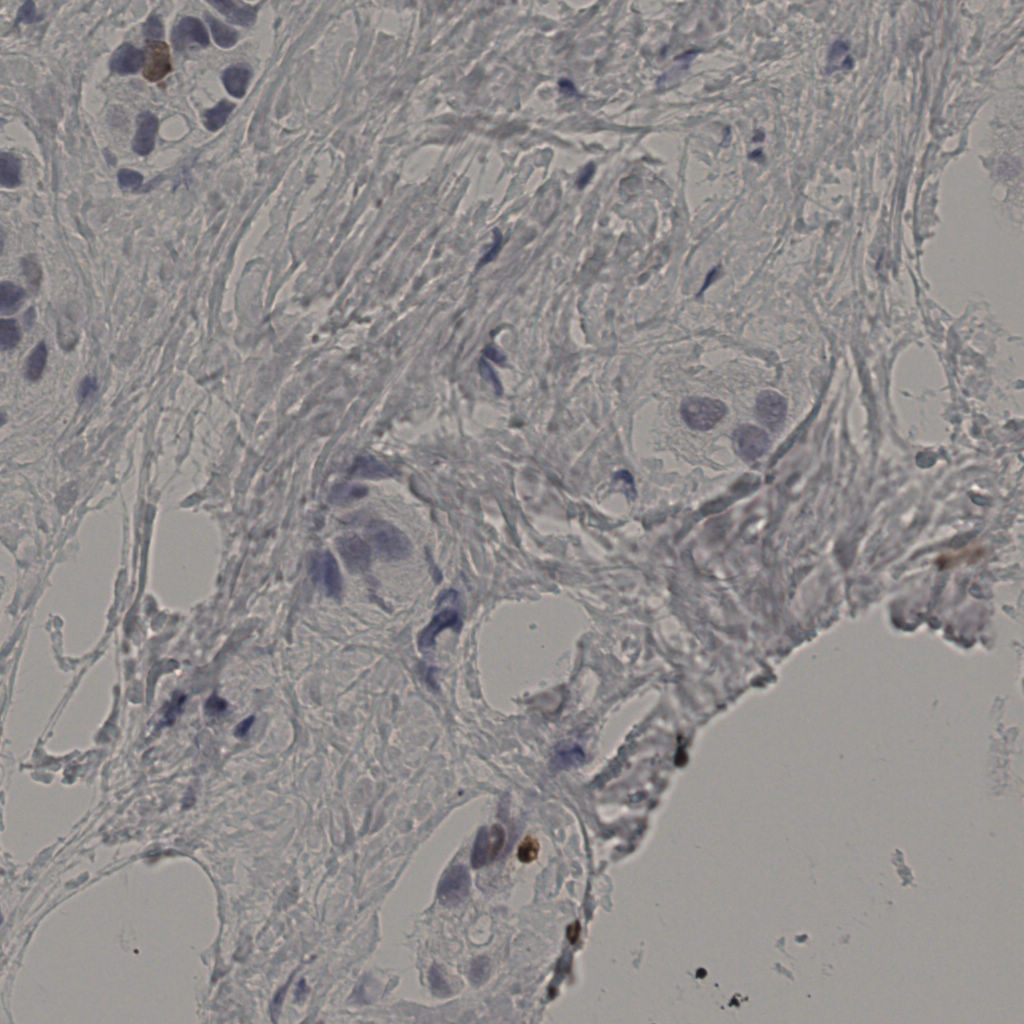

缩略图

标记后

标记前